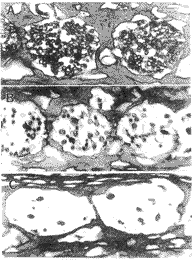

耳蜗铺片显示3组小鼠的毛细胞缺损程度明显不同,见图1。

图1 铺片示耳蜗底回毛细胞

A:出生2个月野生型小鼠

B:出生13个月野生型小鼠

C:出生13个月SOD1基因缺陷型小鼠(下同)

平均耳蜗图显示出生2个月的野生型小鼠毛细胞基本无缺损;出生13个月的野生型小鼠近底回和顶回的外毛细胞有缺损,但内毛细胞基本健全,出生13个月的SOD1基因缺陷型小鼠约有50%的内毛细胞缺损,外毛细胞的损失更为严重,其病变范围从底回向顶回扩展。骨性螺旋板切片显示3组小鼠疆孔内的神经纤维数量明显不同,见图2。